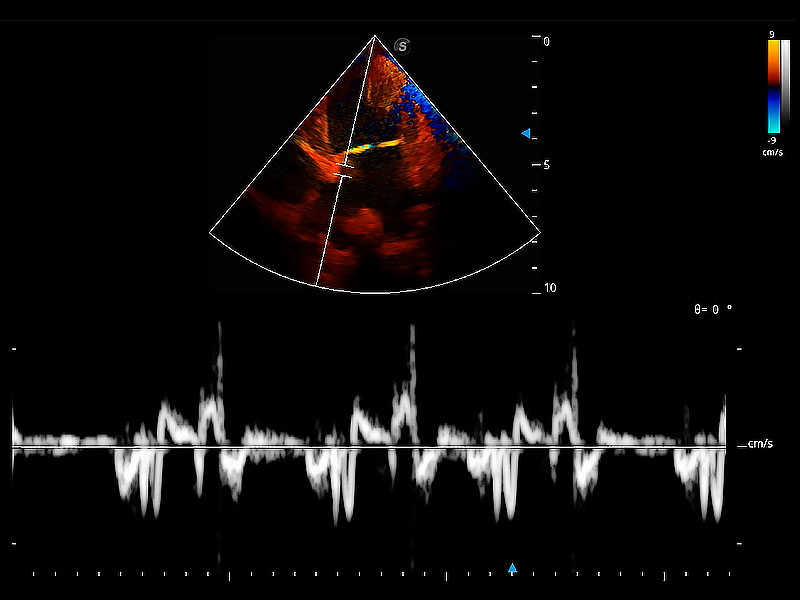

極大提升超低速微細(xì)血流的檢出能力,同時更精準(zhǔn)地濾除軟組織和超聲信號,為獸用醫(yī)生提供以往無法通過常規(guī)血流獲得的疾病診斷信息。

在傳統(tǒng)二維血流成像的基礎(chǔ)上,呈現(xiàn)血流的立體感,具有動感的生命力之美。即便是微小的血管也能輕松應(yīng)對,提高了血流的視覺敏感性。

實(shí)時用顏色表示心肌組織運(yùn)動,觀察和定量組織的運(yùn)動情況,對快速檢測與評估心肌的灌注和活性、電傳導(dǎo)及心肌收縮和舒張功能等均能提供重要的診斷信息。